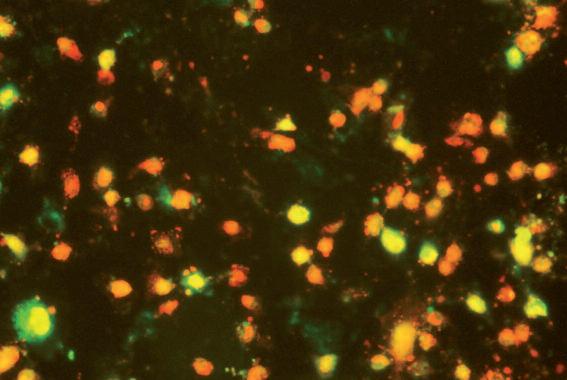

„Brillano di rosso le stelle?”

„La scienza pari all’ar te“ un’idea di August Kowalczyk

„Brillano di rosso le stelle?” immagine al microscopio di cellule tumorali, che per effetto dei micronutrienti si avviano a morire in modo naturale.

Immagine eseguita presso l’istituto di ricerca del Dr Rath a Santa Clara, in California

L’intera galleria di foto è disponibile nel sito: www.dr-rath-humanities-foundation.org/exhibition/index.html.